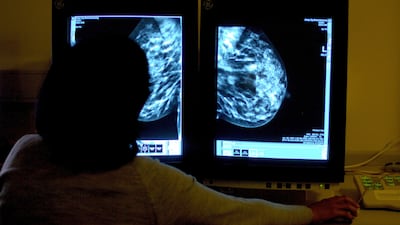

Cancer patients could overwhelm the UK’s National Health Service as more and more people are diagnosed with the disease, a leading charity has warned.

Cases are projected to rise from the current 384,000 a year to 506,000 in 2040, a jump of about a third that would take the number of new annual cases to more than 500,000 for the first time, Cancer Research UK data showed.

The NHS could be “overwhelmed by the sheer volume of new cancer diagnoses”, the charity said.